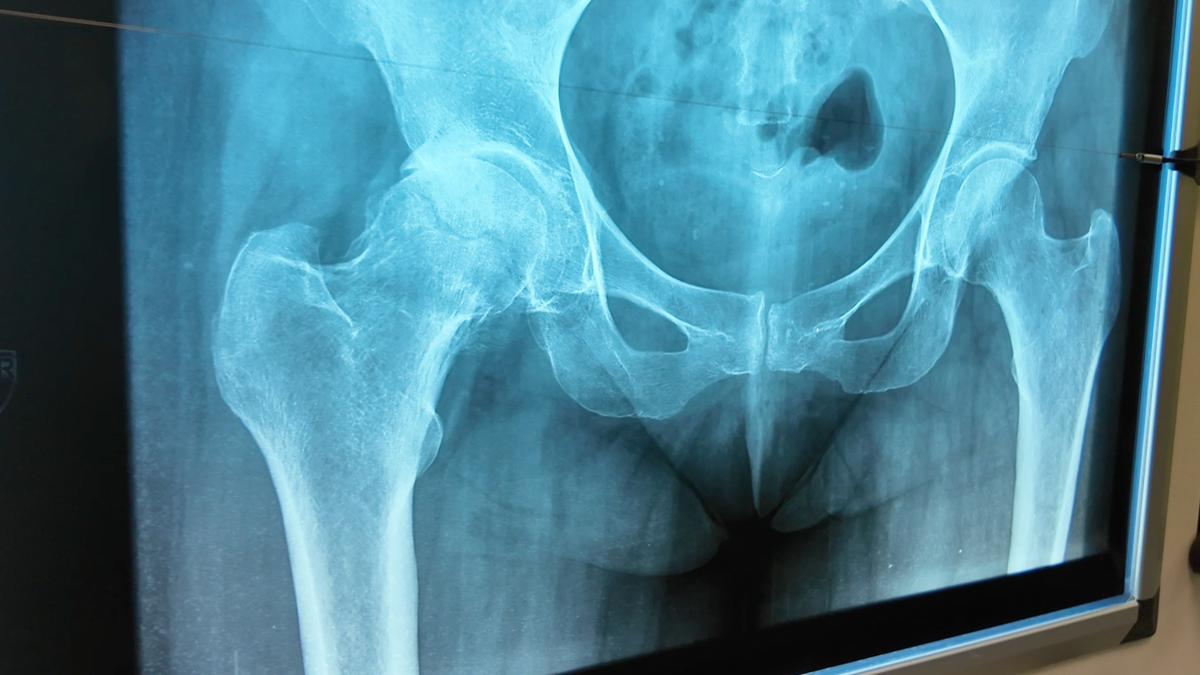

Пациентка 62 лет. Обратилась с диагнозом деформирующий артроз правого тазобедренного сустава (также известный как косартроз).

-2

Проведена операция: тотальное эндопротезирование правого тазобедренного сустава. Протез с бесцементной фиксацией производителя Smith and Nephew. Пара трения: керамика — полиэтилен.